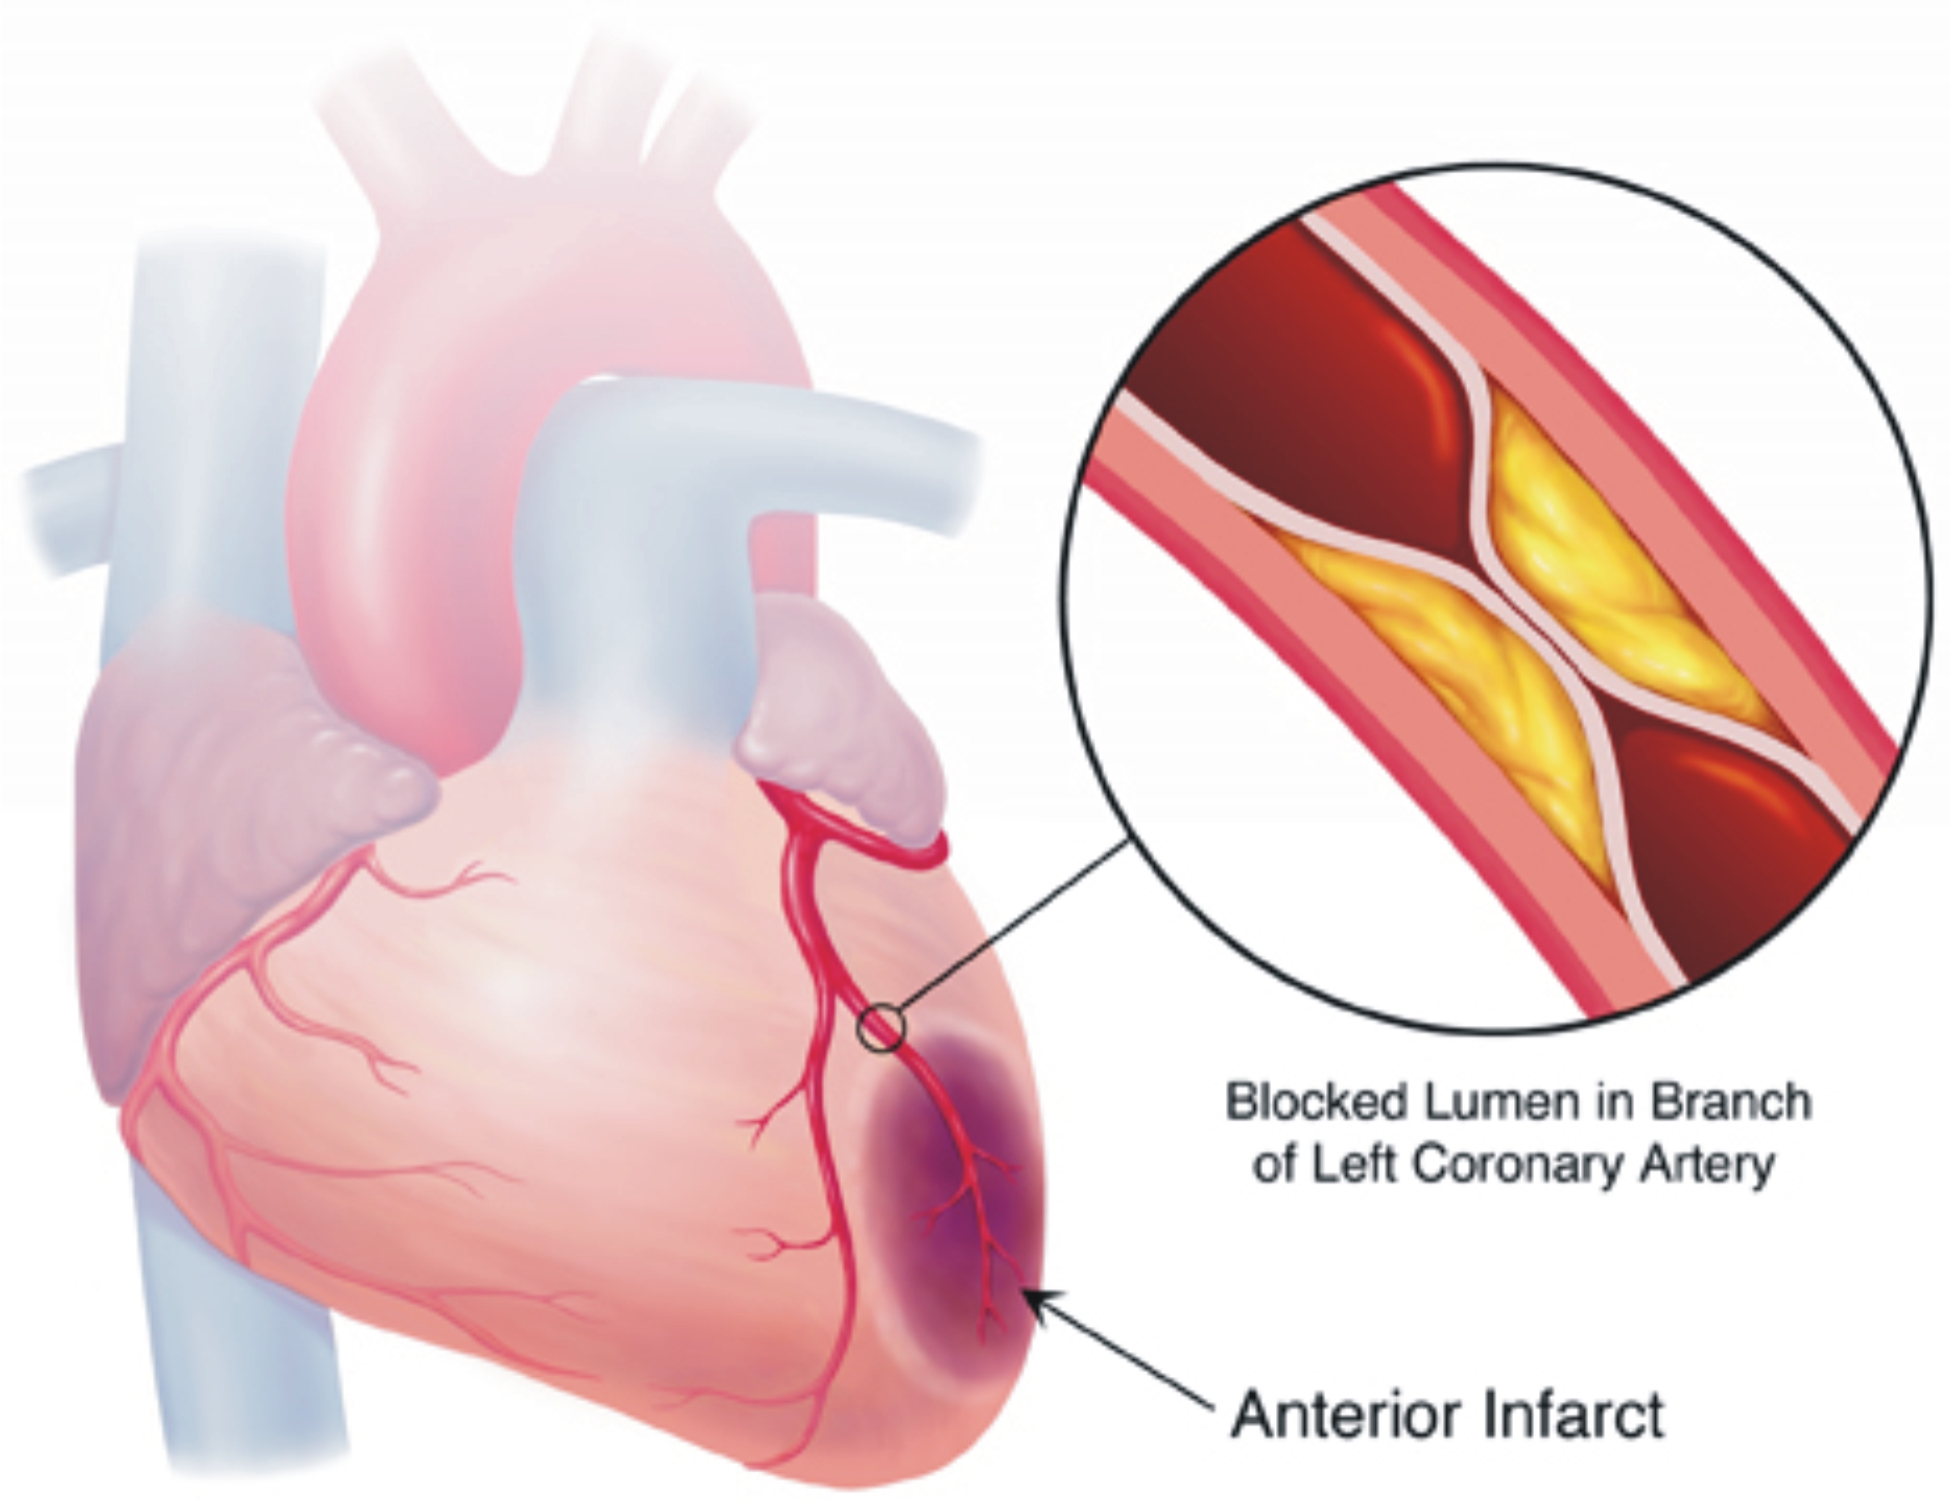

Ischemia is an insufficient supply of blood to an organ usually due to a blocked artery Myocardial ischemia is an intermediate condition in coronary artery disease during which the heart tissue is slowly or suddenly starved of oxygen and other nutrients Ischemia means that there is a reduced blood and oxygen supply to a certain part of the body Locations in the body this condition can affect include the heart intestines brain and limbs Ischemia can happen due to structural or functional problems in the heart but it can have a variety of causes

Ischemic heart disease is heart damage caused by narrowed heart arteries Ischemic heart disease can cause chest pain or discomfort Silent ischemia is when blood flow to the heart is reduced with no obvious symptoms What is myocardial ischemia Myocardial ischemia or cardiac ischemia means your heart muscle is not getting enough blood which contains oxygen and nutrients to work as it should If this lack of blood from your coronary arteries is severe or goes on for more than a few minutes it can damage your heart muscle

Ischemia Meaning - Ischemia is an insufficient supply of blood to an organ usually due to a blocked artery Myocardial ischemia is an intermediate condition in coronary artery disease during which the heart tissue is slowly or suddenly starved of oxygen and other nutrients